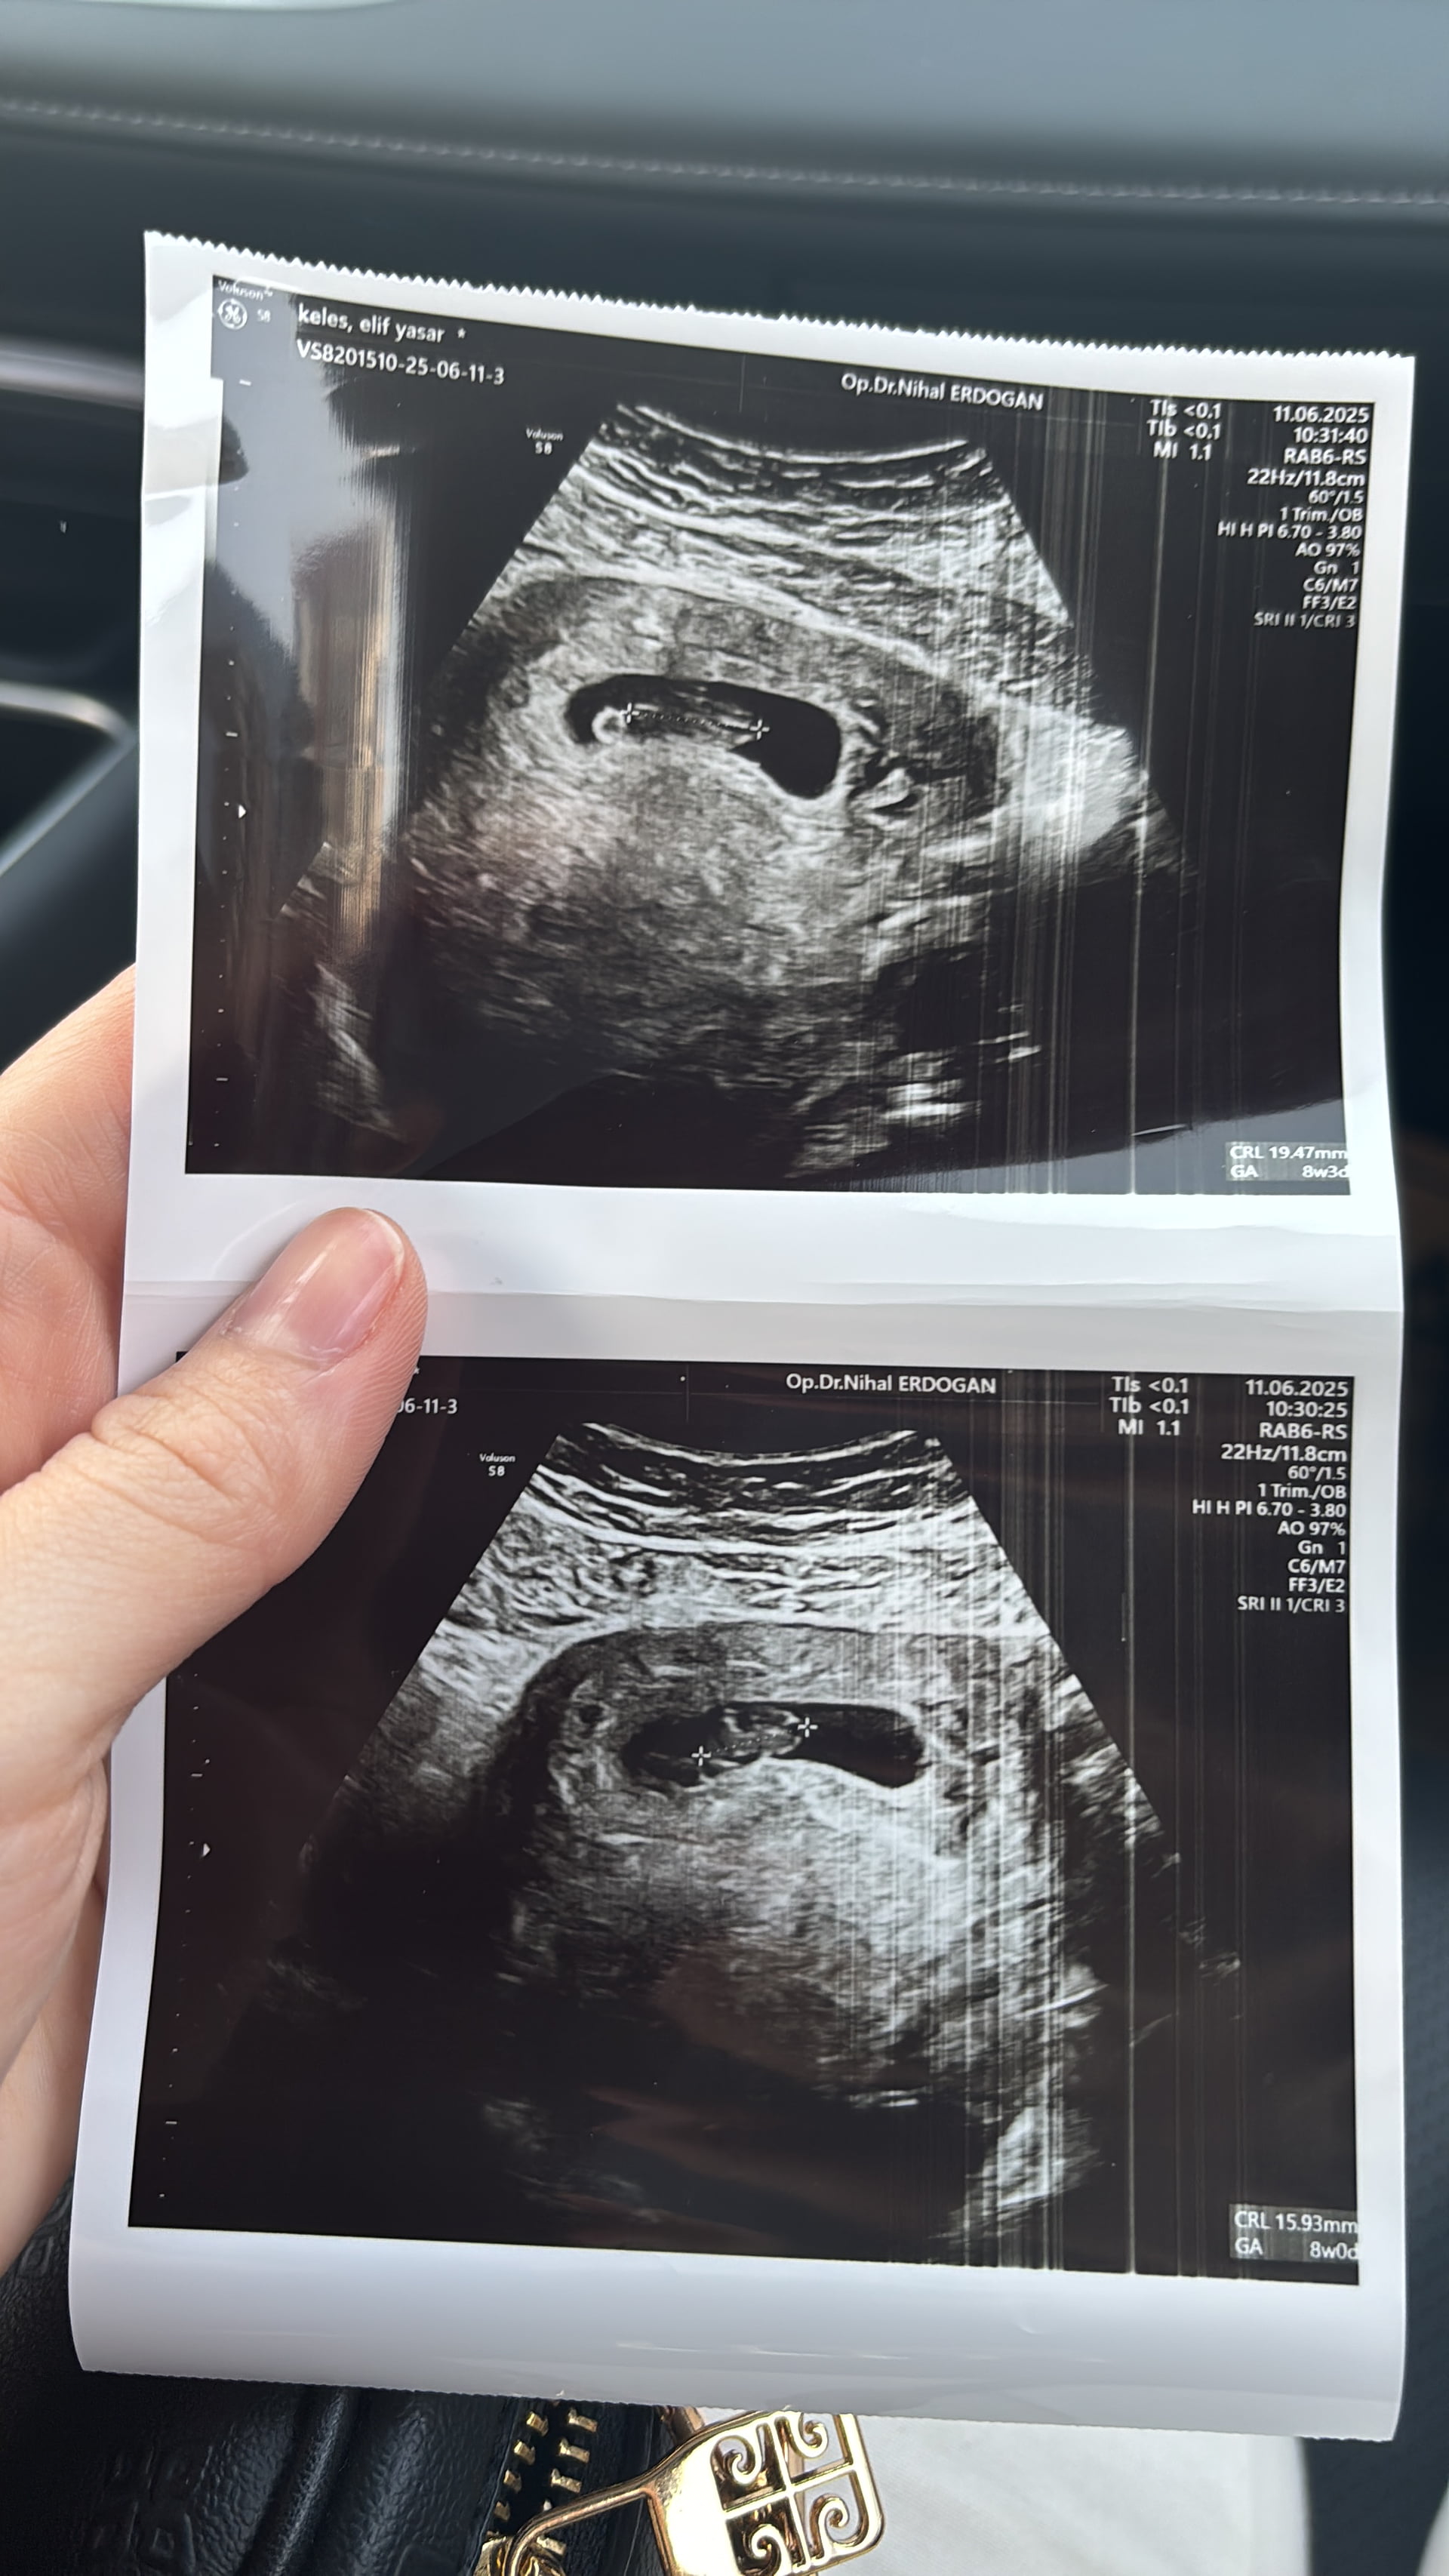

@zey05 bende hamileym ![]()

1 hafta sonra ultrason kağıdını atarım tahmin edersin artık![]()

Yok canım karıştırma ikinciye hamileyim![]()

Elifcim merhaba hataydamı yaşıyorsun doktorun ismini görünce şaşırdım iskenderun gelişimde nail erdoğan